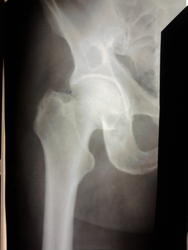

Двухсторонние литические очаги, с четкими, местами склерозироваными контурами. Старый консолидированый перелом левой бедренной кости, после металлоостеосинтеза металлической пластиной. Миеломная или мтс проявили бы себя более агрессивной деструкцией.

tatyana, Вам "зачет"! Здесь действительнро болезнь Реклингхаузена. Наблюдаю данного пациента лет 7. За это время его патологический перелом левой бедренной кости так и не срастается, приобретая все более атрофичный вид в виде перетяжки на уровне излома, потому и держат с металлом до сих пор. Классическая "пастушья палка". Справа в теле подвздошной кости и (менее выраженно) ближе к задней нижней ости, а также в большом вертеле также имеются литические очаги, относительно стабильные за время наблюдения.

Недавно разговаривал с этим пациентом (на ФЭГДС пришел с гастралгией, а у него аденома в ЛДПК нашлась). Со слов: в 15 лет ему выявили остеопороз, пытались обследовать и лечить, причину не выяснили. Отслужил армию. Сломал руку. При обследовании выявлена аденома паращитовидной железы справа. Выполнена правосторонняя гемиструмэктомия с аденомой вместе в 1980 г. Последние годы кальций крови нормальный, но вот кисты костей остаются прежними.